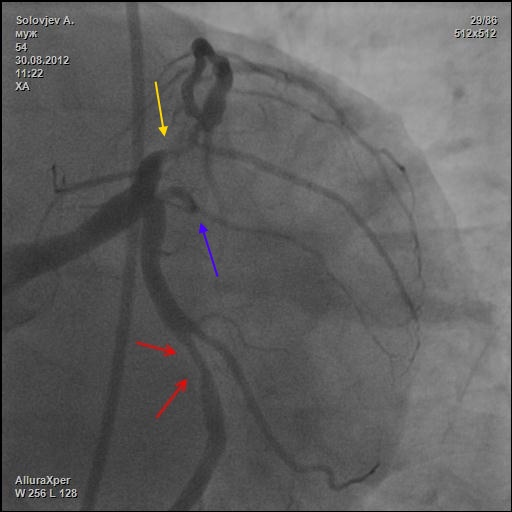

субокклюзия передней

Расценена как окклюзия (желтая стрелка). А другие?

28.jpg

28.jpg [ 49.44 KiB | Просмотров: 27881 ]